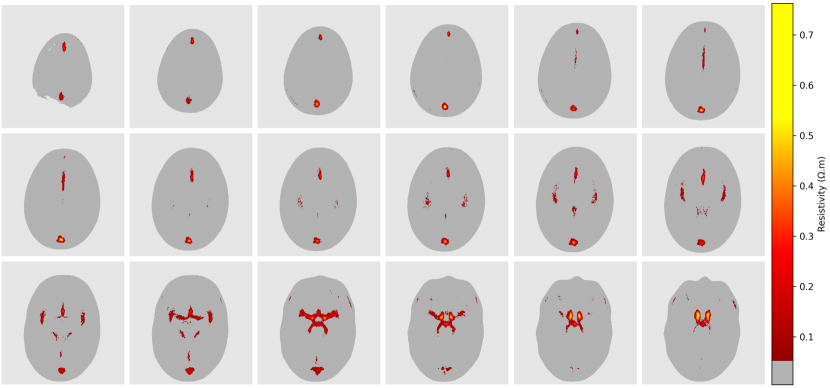

The dynamic component of the atlas was computed following the procedure described in Section 2.2. Transversal slices of the average at 1 kHztimes1kilohertz1\text{\,}\mathrm{kHz} are presented in Figure 8. The main vessels that compose the circle of Willis in the base of the cranial cavity, the dense arterial vascularization in the insular cortex, and the superior sagittal sinus are visible.

Figure 8: Transversal slices of the average image of the segmented vessels filled with still blood at 1 kHztimes1kilohertz1\text{\,}\mathrm{kHz}. Small values were masked in grey to emphasize the structure of the main vessels.